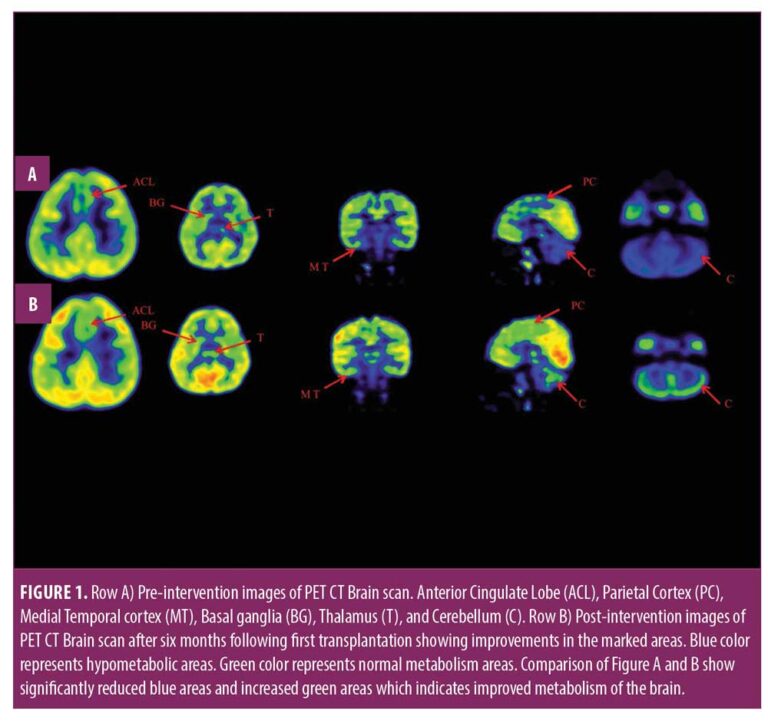

本報告中,我們治療了一名患有痙攣性雙癱性腦癱的兒童,在對康復反應有限后,采用了多種細胞療法。臨床改善的結果與客觀量表相關,例如粗大運動功能測量 (GMFM)、粗大運動功能分類系統 (GMFCS) 以及功能獨立測量 (FIM) 和 (PET CT) 腦成像研究。

在認知上,由于他定期上學,他的注意力持續時間和坐姿耐受力也得到了改善。GMFM分數從60.67提高到67。GMFCS等級由3級提升至2級;FIM評分從97分提高到99分。比較第一次細胞治療之前和之后7個月期間進行的腦部PET CT掃描結果,發現前扣帶回葉、頂葉皮層、內側顳葉皮層、丘腦、基底神經節和小腦(表1)。

這項研究表明,多種干細胞療法結合神經康復可有效改善腦癱患者的粗大運動功能和功能獨立性。自體BMMNC多次移植后進行強烈的神經康復可加快神經再生過程,這反過來又反映了患者殘疾程度和生活質量的積極結果。PET CT掃描可以有效地用于監測干預后細胞水平發生的變化。因此,多細胞療法是安全、可行的,并且可以有效地與腦癱的神經康復相結合作為增強治療。